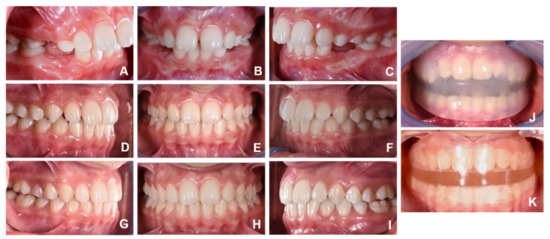

- Dental outcomes: an OVJ reduction (−2.64 mm p = 0.0002) without significant changes in the incisors inclination and position: Is^Ii (1.62 p = 0.4836); Is:NA (0.58 mm, p = 0.2822); and Ii:NB (0.92 mm, p = 0.0524);

- Airways outcomes: significant changes were found in the width of the upper airways, SPAS (2.21 mm, p = 0.0099), while the improvement in the middle and lower pharyngeal space was not significant, i.e., MAS (1.41 mm p = 0.0786) and IAS (1.64 mm p = 0.1342).